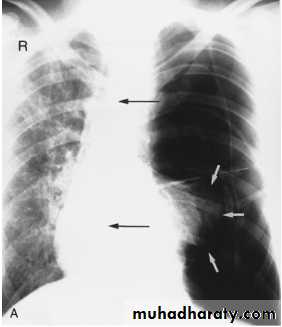

Pleural Effusion on Chest Radiographs.

Posteroanterior (A) and lateral (B) chest radiographs demonstrate the typical meniscoid appearance (arrows) in a patient with a left pleural effusion

Hydropneumothorax.

When fluid and air are present in the pleural space on an upright chest x-ray, a perfectly straight horizontal line will extend all the way from the spine to the edge of the pleural cavity. In this patient, a loculated right basilar hydropneumothorax is present.

The air/fluid interface is easily seen (arrows). If this were a lung abscess, the air/fluid level would be very unlikely to extend all the way from the medial to the lateral aspect of the hemithorax.